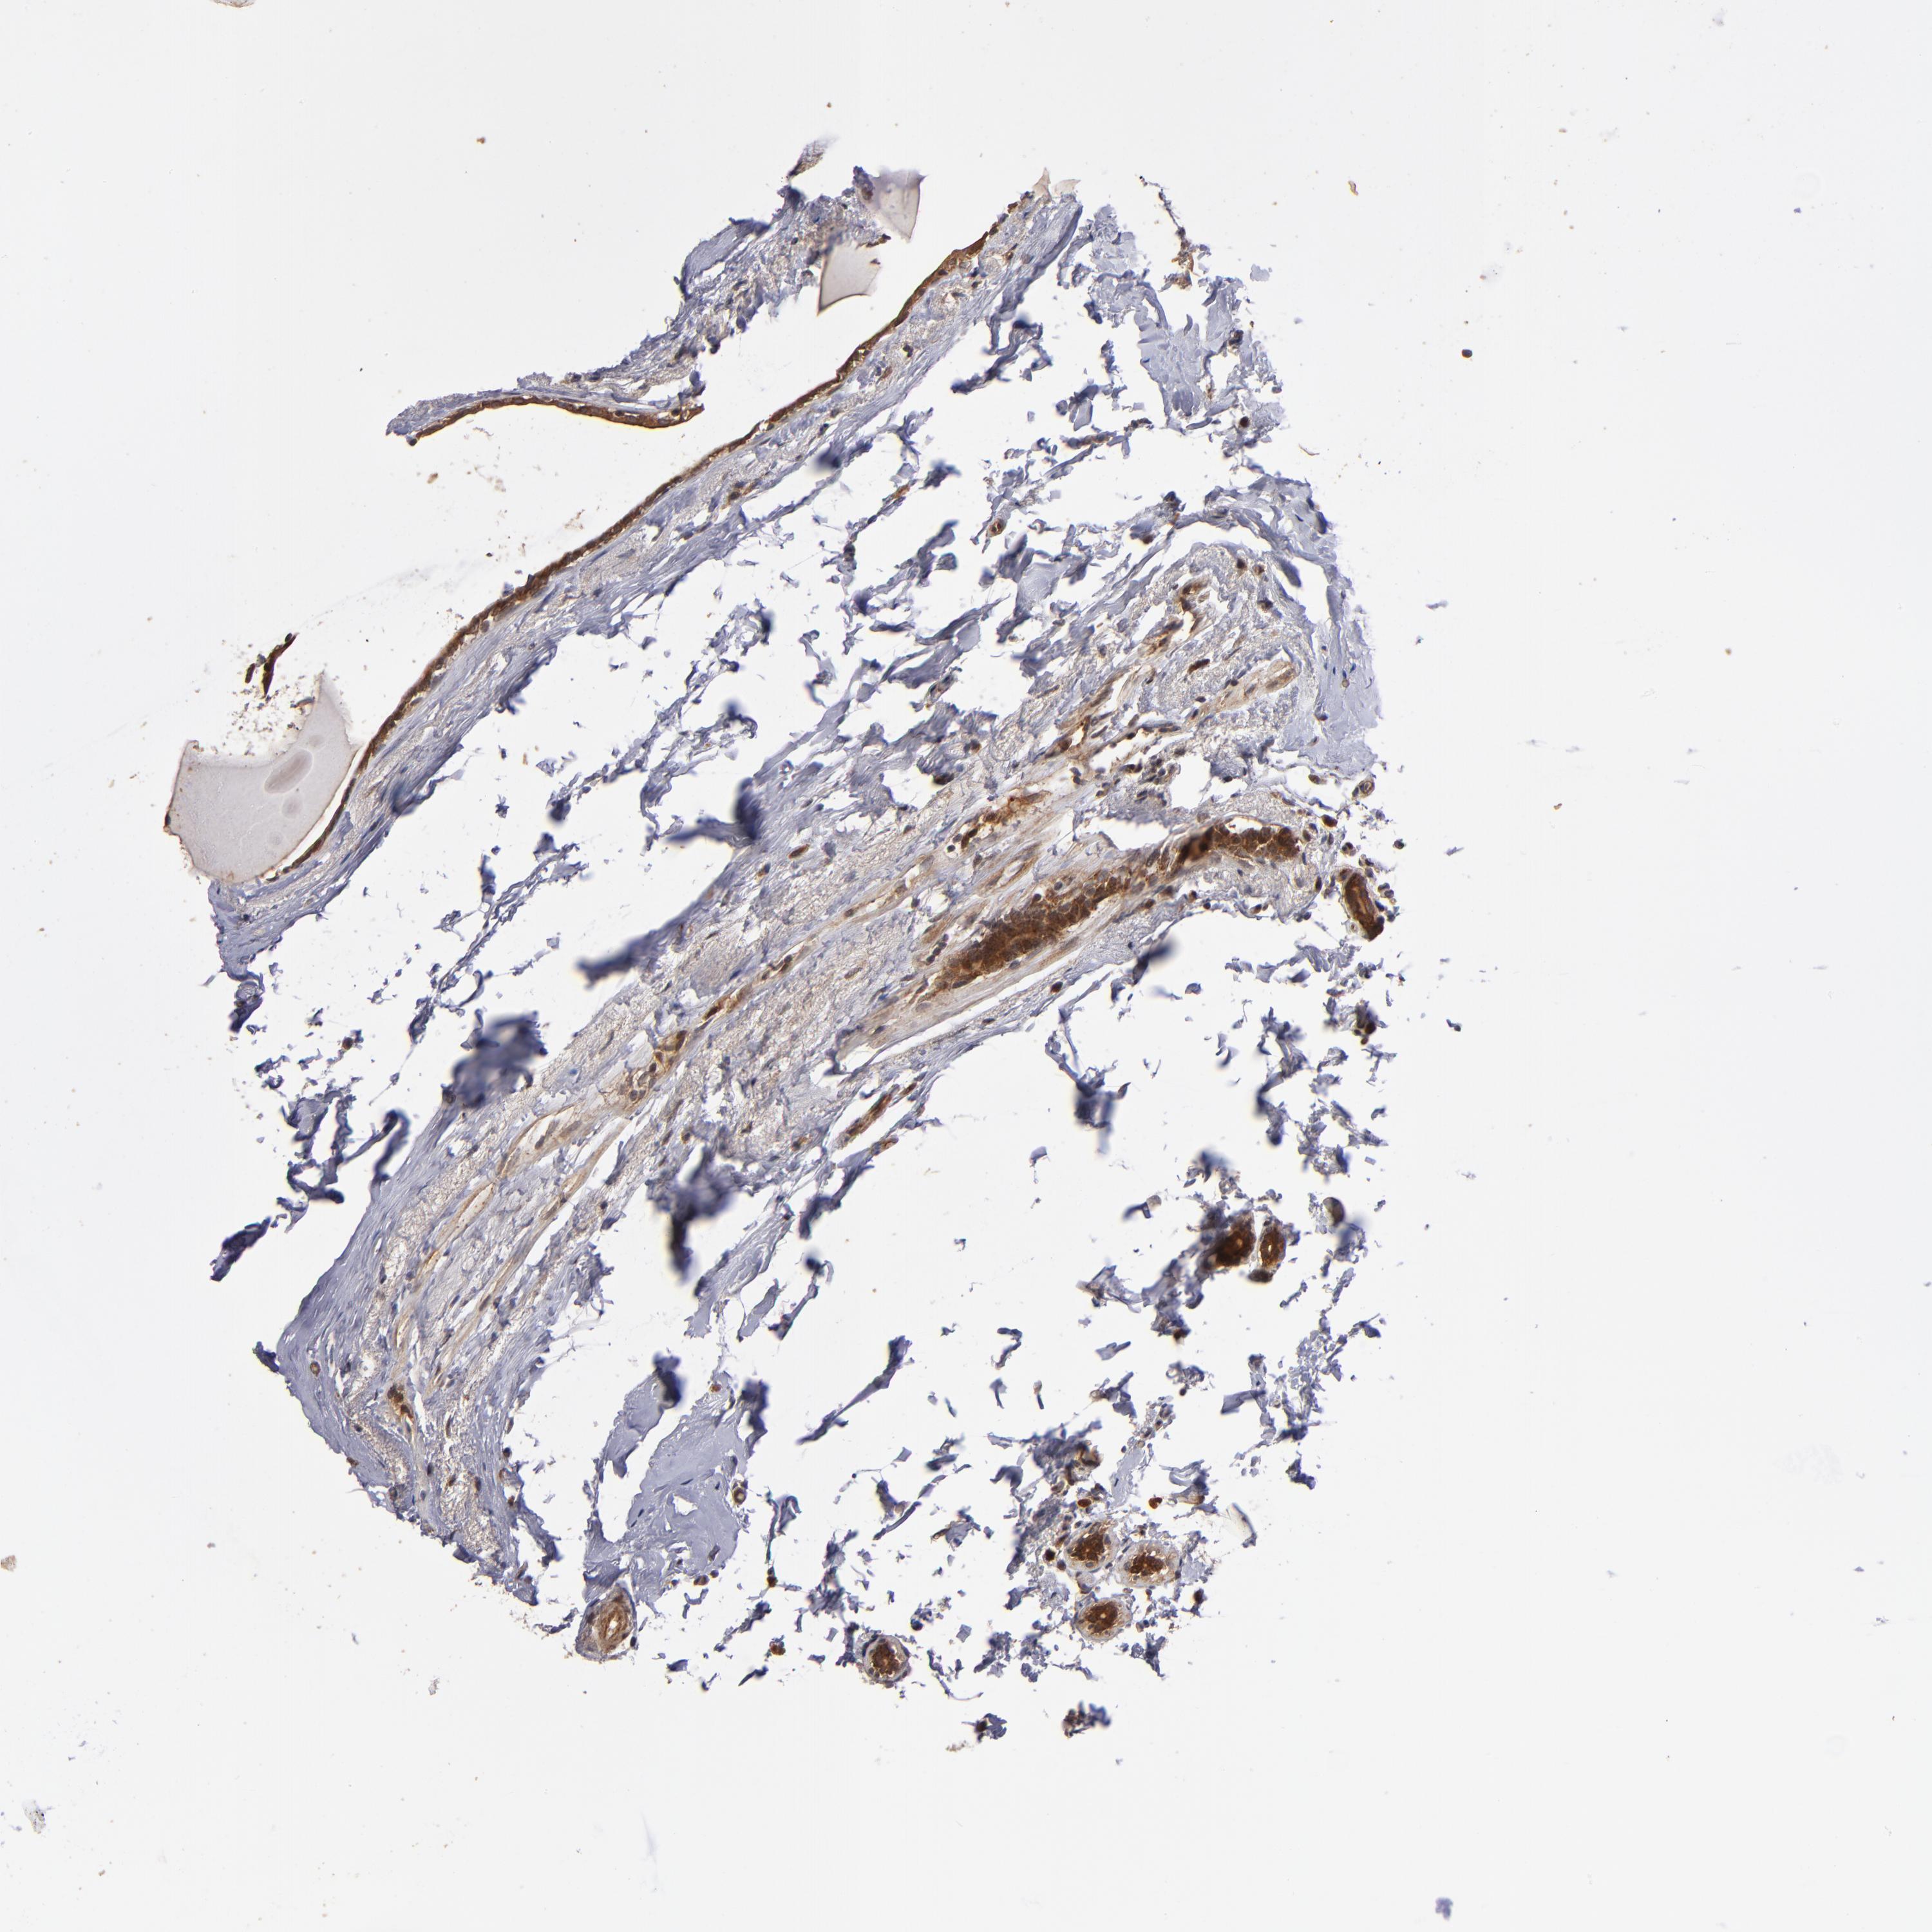

BRCA TCGA BRCA VALIDATION PROTEIN EXPRESSION

ANTIBODIES

AND

VALIDATION